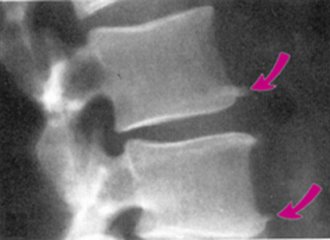

前面我们也介绍过骨刺的发生原因和产生机理。骨刺(骨赘)是人的机体对于应力、磨损、炎症等的一种反应,通过这种适应性反应,可以起到稳定局部环境,维持机体的功能,从这个角度上说,骨刺是一种正常的代偿反应,并非多余。

虽然骨刺是医生诊断骨性关节炎的一个依据,但绝大多数不是引起局部疼痛的真正原因,更不是它直接引起疼痛症状。只有当局部的骨刺对周围的软组织产生顶压等刺激时,才会引起局部的疼痛症状,并且这种情况非常少见。

导致关节疼痛的主要原因是关节软骨损伤、半月板磨损、关节力线改变等。因而相应的治疗需要在准确把握病因的基础上治疗才是正确的选择。